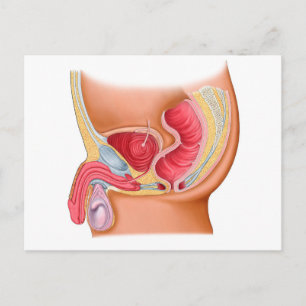

Anatomi hos kvinnlig kropp med reproduktionsorgan hälsningskort

Försäljningspris 49,00 kr. Ursprungligt pris 54,00 kr.

Medicinsk illustration av en Rectourethral Fistula Hälsningskort

Försäljningspris 49,00 kr. Ursprungligt pris 54,00 kr.